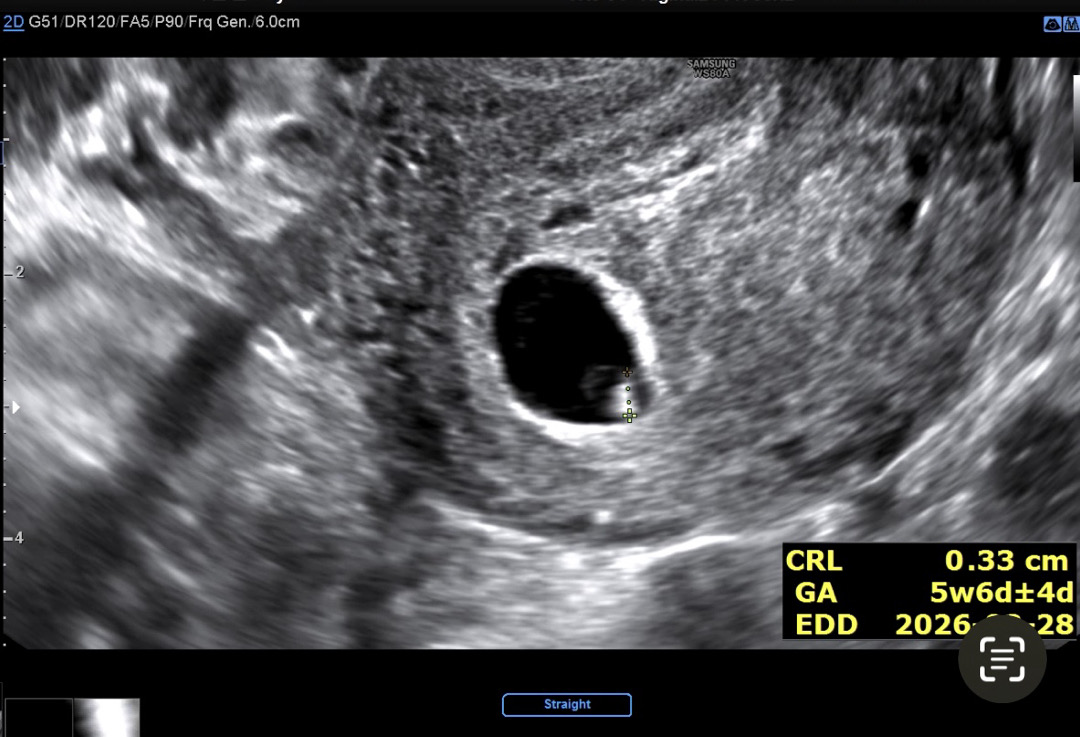

오늘 네이버주수기준 6주6일이라 심장소리 들으러 다녀왔어요 아가 크기가 0.33cm에 심소가 117 이라 주수가 5주6일로 일주일 밀렸는데 병원에서는 정상범위라고 걱정하지 마라고하시지만 계속 걱정이 되는 건 어쩔 수 없네요ㅠ 이 주수에 이정도로 확인하셨다가 2주뒤에 건강히 확인하신 분 댓글 부탁드려요ㅠ 그리고 선생님이 재주신 아기크기보다 제가 초음파영상 이리저리 돌려보며 본 아기가 더 커보이는데 크기 재는 방식에따라 다른거겠죠??